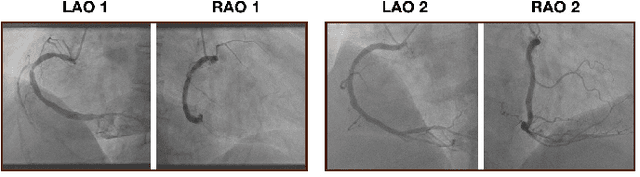

Abstract:The evaluation of obstructions (stenosis) in coronary arteries is currently done by a physician's visual assessment of coronary angiography video sequences. It is laborious, and can be susceptible to interobserver variation. Prior studies have attempted to automate this process, but few have demonstrated an integrated suite of algorithms for the end-to-end analysis of angiograms. We report an automated analysis pipeline based on deep learning to rapidly and objectively assess coronary angiograms, highlight coronary vessels of interest, and quantify potential stenosis. We propose a 3-stage automated analysis method consisting of key frame extraction, vessel segmentation, and stenosis measurement. We combined powerful deep learning approaches such as ResNet and U-Net with traditional image processing and geometrical analysis. We trained and tested our algorithms on the Left Anterior Oblique (LAO) view of the right coronary artery (RCA) using anonymized angiograms obtained from a tertiary cardiac institution, then tested the generalizability of our technique to the Right Anterior Oblique (RAO) view. We demonstrated an overall improvement on previous work, with key frame extraction top-5 precision of 98.4%, vessel segmentation F1-Score of 0.891 and stenosis measurement 20.7% Type I Error rate.